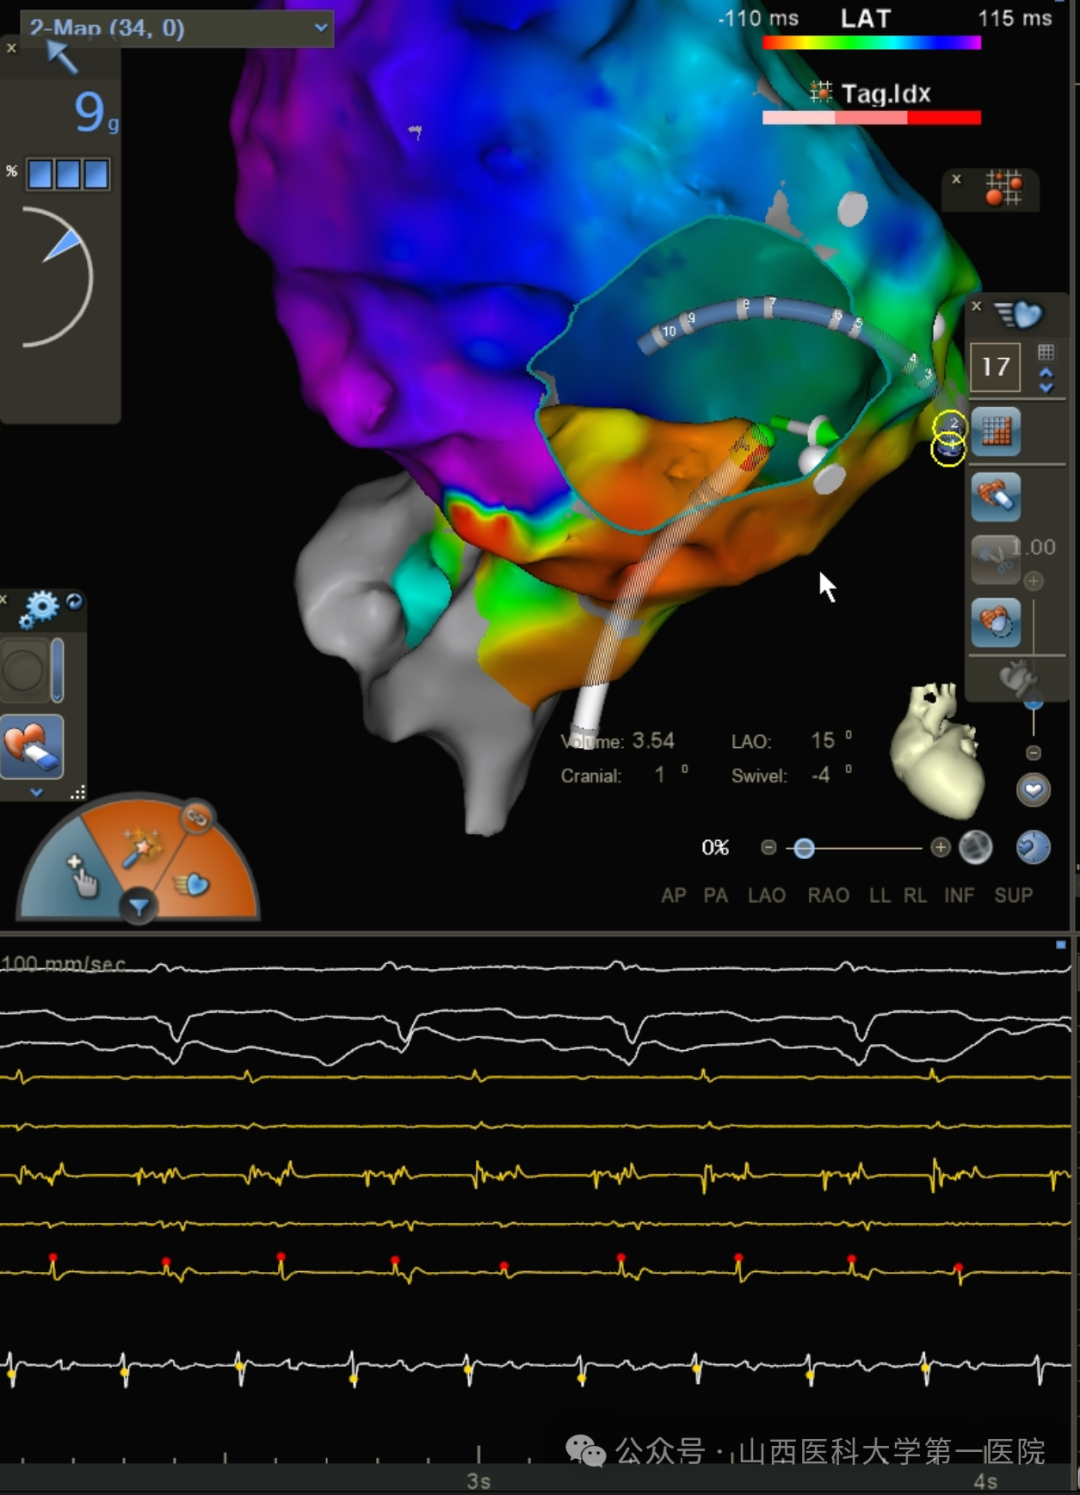

更换Vizigo鞘管进行三尖瓣峡部消融,房扑周长逐渐延长至240-250ms,直至房扑终止。在ICE指引下,导管配合可调弯鞘管行倒U法贴靠,对游离壁侧补充消融,验证CS口和右房游离壁底部双向传导阻滞,起搏冠状窦口下沿三尖瓣环标测,传导顺序符合峡部线阻滞情况,心房Burst 刺激未诱发心动过速。观察20min后重复电生理检查结果同前,手术结束术后心电图示窦性心律。